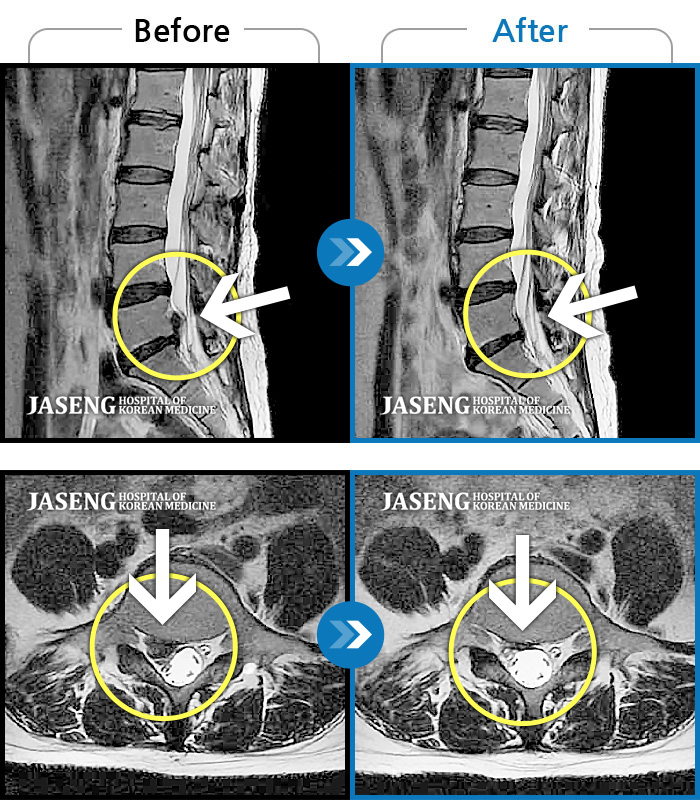

허리디스크

수원 · 김태성 원장

우측 허리, 엉치 통증으로 활동하기 힘든 상태

촬영시기

2019.09.11 ~ 2020.04.04

2022.03.25